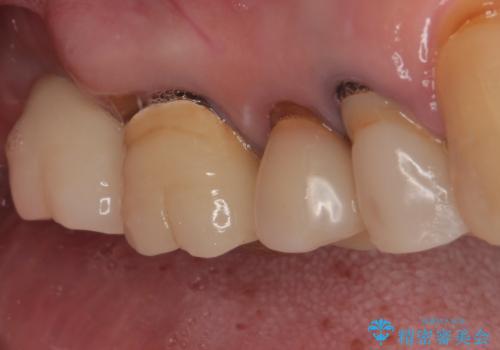

抜歯後2ヶ月でのインプラント埋入を行いましたが、骨の再生は不十分でした。

骨量は不十分でしたが、デンサーバーを用いることで無事に埋入することができ、その後は速やかに補綴治療を行うことができました。